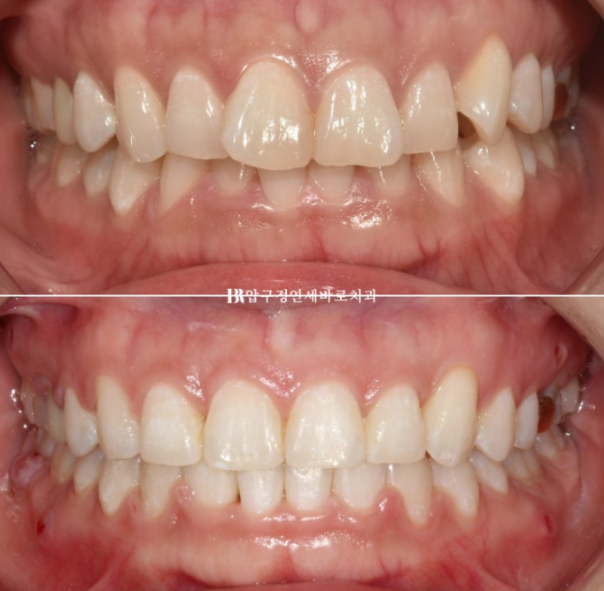

23.04~24.10

작년 4월 돌출과 덧니 때문에 찾아오신 30대 환자분입니다.

지방에서 오신 분입니다.

윗니 아랫니가 깊게 물리는 과개교합, 덧니, 중심선 불일치가 보입니다.

치료시작 1년 7개월째 치료를 종료했습니다.

중심선은 정확히 일치하고 앞니가 깊게 물리는 과개교합은 해결이 되었습니다.

잇몸 노출량이 줄면서 잇몸미소 거미스마일 많이 좋아졌죠?

소량의 입동굴이 생겼고 과하지 않은 입동굴은 여성스러운 미소 심미를 개선시킵니다.

돌출되지도 옥니처럼 쓰러지지도 않는 일자로 딱 떨어지는 적절한 앞니 각도 개선된 잇몸 노출량

비포 애프터 사진을 보면 환자분들은 그제서야 내가 잇몸이 원래 많이 보였구나 하고 감탄하십니다.